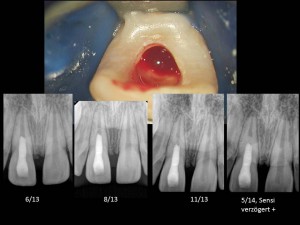

Der Teufel steckt im Detail 9. Dezember 2014 von Michael Arnold · Published 9. Dezember 2014 · Last modified 30. April 2015